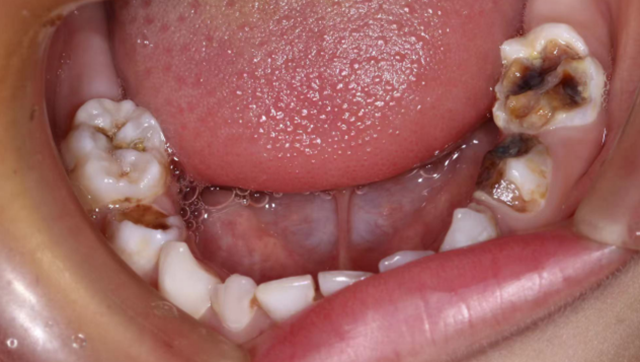

首先患儿坏牙多,就诊次数多,增加了就诊成本;其次许多口腔问题需要局麻伴有疼痛,患儿不配合还容易对口腔治疗产生阴影,例如根管治疗、拔除难度较大的牙、唇舌系带修整术等,这时全麻下舒适化口腔治疗就是最佳的选择。

全麻下儿童口腔舒适化治疗适用于哪些人?

1.心理、情感或智力障碍或全身系统性疾病而不能配合的患者;

2.3岁以下,需要立即治疗,因年幼不能配合的低龄患儿;

3.极度恐惧、紧张或不能交流的儿童或青少年,短期内行为不能改善者;

6.多颗牙需要治疗,家长或患儿不能多次就诊者。